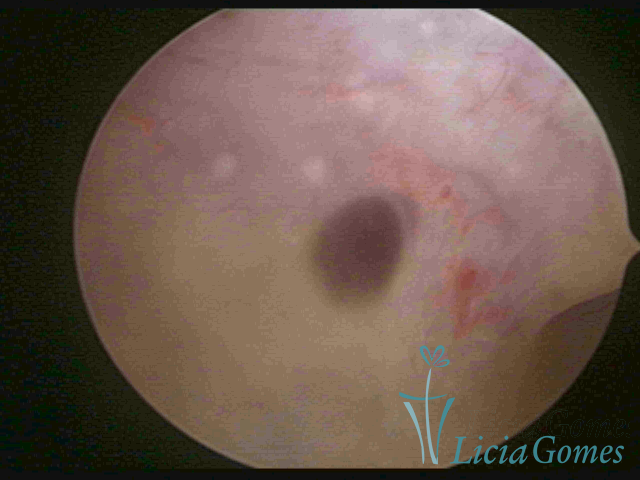

ADENOMYOSIS

The presence of endometrial tissue on the muscular layer of the uterus.

Video hysteroscopy allows diagnosing the lesions next to the superficial myometrial layers next to the endometrium, allowing the view of in situ, purplish, or chocolate brown lesions.